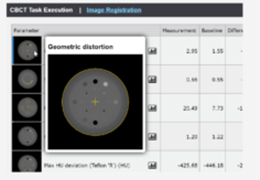

Load DICOM data directly from PACS, CD/DVD, USB, and local computer.

Upload DICOM data to your PACS directly from referral patient CD/DVD and local computer.

Easy to use patient search to locate patient data on your PACS.

Designed mainly for CT and MR DICOM modalities.